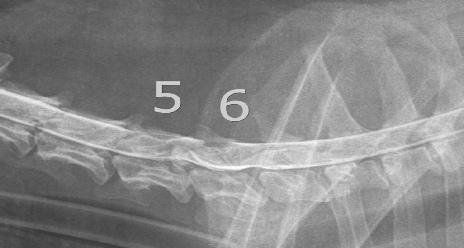

I metodi diagnostici utilizzati dai neurologi veterinari comprendono

esame fisico e racolta dell'anamnesi,

valutazione radiografica (in bianco nero e con mezzo di contrasto-MIELOGRAFIA)

analisi del liquido cerebrospinale,

risonanza magnetica e TC,

test elettrodiagnostico che comprende la valutazione della velocità della conduzione nervosa.

esame di potenziali evocati uditivi-BAER.